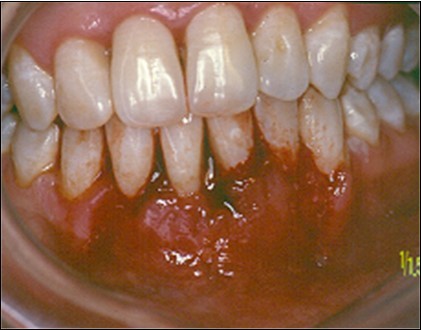

Figure 2.After initial therapy

After initial therapy